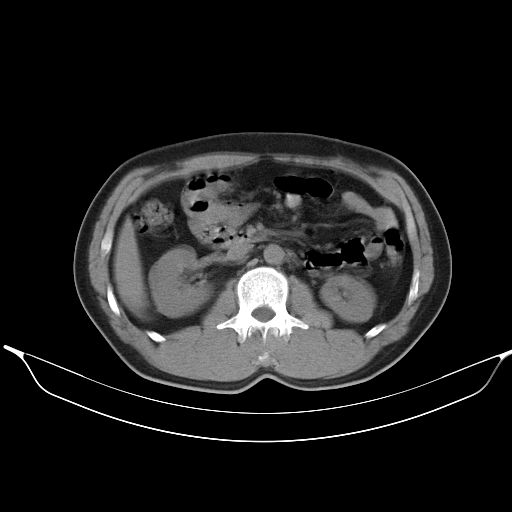

标题: CT25490:男,40岁,体检发现;无其它不适。 [打印本页]

标题: CT25490:男,40岁,体检发现;无其它不适。

2、轻度脂肪肝。

1、均为转移,原发灶不在肺内。2、肺癌肺转移。